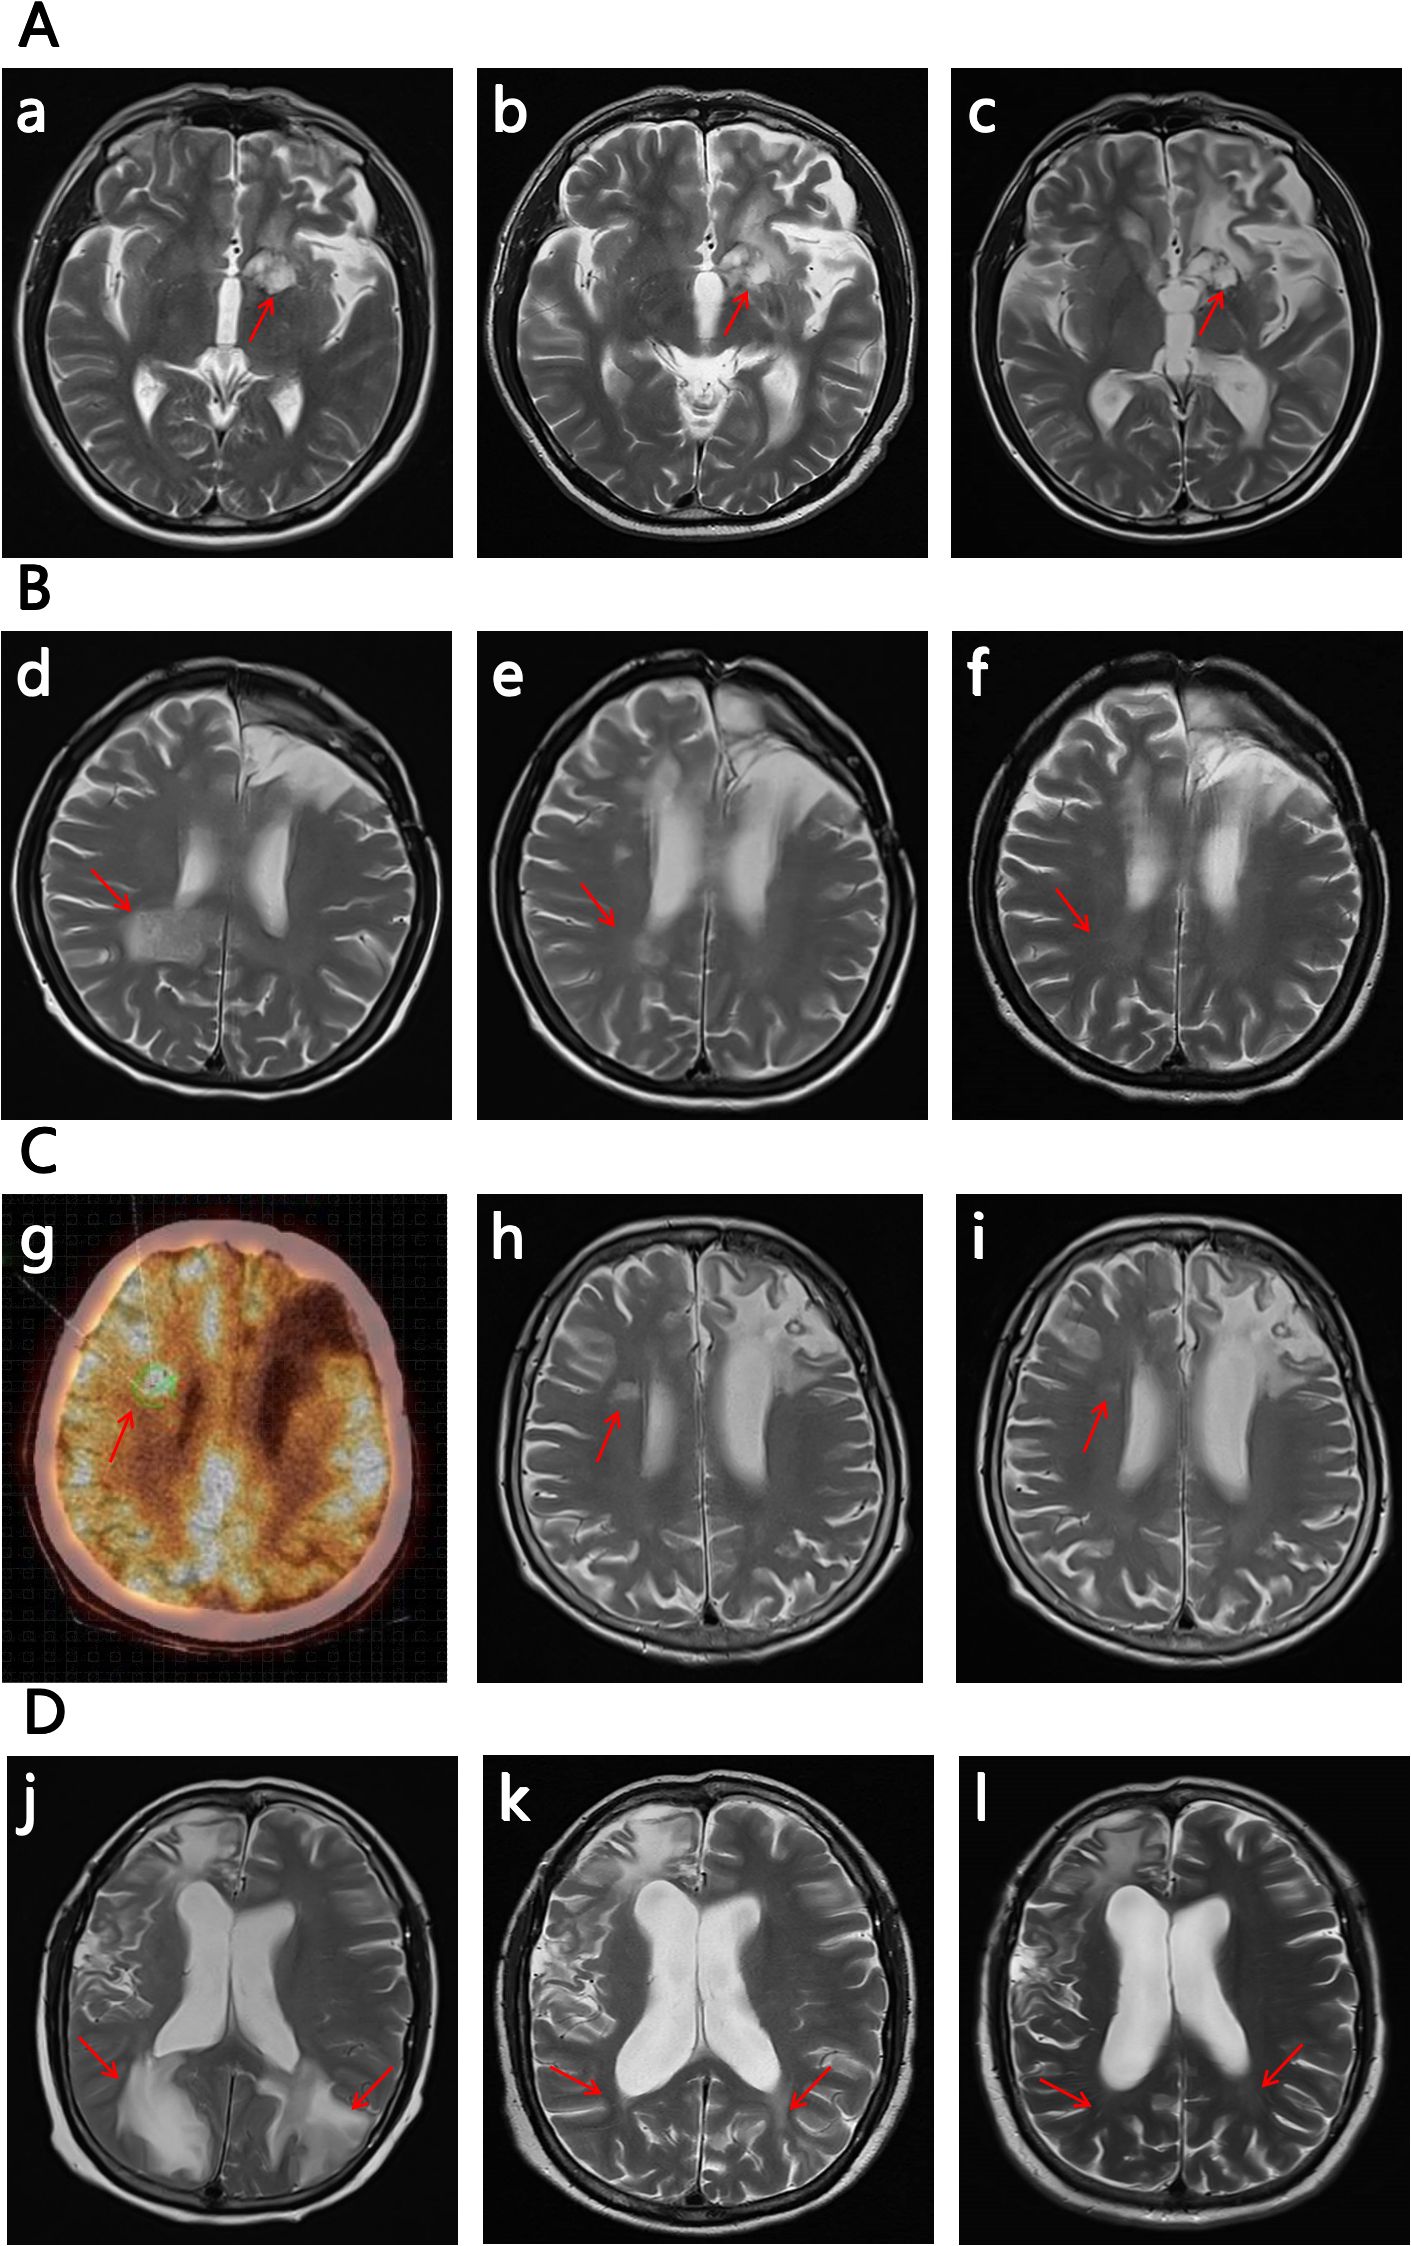

The No.1 patient was a 54-year old man with PCNSL. His lymphoma lesions were located in the left paraventricular basal ganglia. After 4 cycles of RTM+BTKi (rituximab 375mg/m2 d1, thiotepa 30mg/m2 d2, methotrexate 3.5g/m2 d3, orelabrutinib 150mg qd) chemotherapy, he achieved CR. Then he received another 2 cycles of RTM+BTKi chemotherapy and 2 cycles of rituximab targeted therapy. However, 1 month later, he went to hospital again for blurred vision, and was diagnosed relapsed. For the first relapse of lymphoma, he received 1 cycle of chemotherapy with RTCS (rituximab 375mg/m2 d1, thiotepa 30mg/m2 d2, cytarabine 2g/m2 q12h d3~d4, selinexor 60mg qw), then a WBRT with 40Gy, then a high-dose thiotepa-based conditiong regimen, and then a successful ASCT. But unfortunately, in 2024-12, 3 months later after ASCT, he developed weak limbs and walking disorder, and was confirmed relapsed again. For the second relapse, as a variety of therapies had been used previously, he started to try a treatment with glofitamab combined with lenalidomide. Glofitamab was administered intravenously with step-up dose till up to 30mg, and lenalidomide was orally administered 15mg/day continuously. He achieved PR after 2 cycles of therapy of glofitamab combined with lenalidomide, although he still kept in PR in the following therapy, his tumor decreased and presented with no contrast enhancement by MRI, then he got very close to CRu after 4 cycles (Figure 1). During therapy, the patient was monitored carefully. Transient grade 1 CRS and ICANS once occurred after the first glofitamab administration, but no other adverse events (AE) were observed during the following treatment.

Figure 1

Figure 1. The images of the 4 R/R CNSL patient (the subfigure g was by PET-CT, while others were all by MRI). The significant decrease in the size and contrast enhancement of the CNS lesion (arrows) on T2-weighted post-gadolinium contrast axial images show the response to the treatment (for subfigure g the arrow indicates the location of relaspsed tumor). The positions pointed by the arrows are the locations of the tumor, and the other abnormalities on the images are due to the craniotomy. (A) No.1 patient: (a) on 2024/12/02 at relapse before the therapy of glofitamab combined with lenalidomide; (b) on 2025/02/15 after 2 cycles of the therapy; (c) on 2025/04/02 after 4 cycles of the therapy. (B) No.2 patient:(d) on 2024/10/19 at relapse before the therapy of glofitamab combined with lenalidomide; (e) on 2024/12/05 after 2 cycles of the therapy; (f) on 2025/01/25 after 4 cycles of the therapy. (C) No. 3 patient: (g) a PET-CT scan on 2024/12/02 at relapse before the therapy of glofitamab combined with lenalidomide; (h) on 2025/01/14 after 2 cycles of the therapy; (i) on 2025/03/07 after 4 cycles of the therapy. (D) No. 4 patient. (j) on 2025/03/28 at relapse before the therapy of glofitamab combined with lenalidomide; (k) on 2025/05/15 after 2 cycles of the therapy; (l) on 2025/06/23 after 4 cycles of the therapy.

The No. 2 patient was a 58-year old woman with PCNSL. Her lymphoma lesions were located mainly in the right frontal lobe, corpus callosum, insular lobe, and partly in the right medial splenius capitis lymph node and bone marrow. She attained CR after 4 cycles of RTM+BTKi (rituximab 375mg/m2 d1, thiotepa 30mg/m2 d2, methotrexate 3g/m2 d3, orelabrutinib 150mg qd) chemotherapy. Then for subsequent treatment, she only agreed to receive orelabrutinib 150mg qd and refused other chemotherapy and WBRT. In 2024-10, 6 months later after the last chemotherapy, she presented with nausea, poor appetite, listlessness, and lethargy. Further examination confirmed relapse in the right posterior horn of the ventricle and the left cerebellum. At the time of recurrence, her physical condition with ECOG score >3 did not allow high-dose chemotherapy and ASCT. Then she received the therapy with glofitamab combined with lenalidomide. After 2 cycles of therapy she achieved CRu (Figure 1). She had grade 1 CRS and ICANS, as well as grade 2 myelosuppression in only the first and second cycles of glofitamab administration, but she recoverd soon after symptomatic treatment. By now she keeps in CR and is still in the 10th cycle of the therapy with glofitamab combined with lenalidomide.

The No.3 patient was a 69-year old woman with PCNSL. Her lymphoma lesions were located in the left frontal lobe and basal ganglia. At first, She received 4 cycles of chemotherapy with RT+BTKi (rituximab 375mg/m2 d1, thiotepa 30mg/m2 d2, orelabrutinib 150mg qd), and then she achieved CR. But one day after that, she accidentally got a pulmonary tuberculosis which interupted the chemotherapy, and she started to be treated with only orelabrutinib. In 2024-12, 8 months after the interuption of chemotherapy, the PCNSL recurred near the right lateral ventricle of the centrum semiovale. In consideration of the patient’s advanced age, poor physical condition, and history of pulmonary tuberculosis, intensive chemotherapy and ASCT were not recommended, besides, she also refused WBRT. Then she received the therapy of glofitamab combined with lenalidomide. She got PR after 2 cycles of treatment, then got CRu after the 4th cycle (Figure 1). She had a transient symptom of grade 1 CRS druing the first cycle of glofitamab administration. No ICANS or other AE was observed during subsequent treatment. Now she is still in the 8th cycle of the therapy, and still in CRu.

The No.4 patient was a 51-year old woman with SCNSL. Eight years ago, she had a primary breast DLBCL, and received ASCT after 4 cycles of chemotherapy with R-CHOP combined with MTX. In 2024-05, she developed epilepsy and consciousness disturbance without any obvious cause. Imaging examination showed a tumor in the right frontal lobe of her brain. Then, a total body positron emission tomography-computed tomography (PET-CT) showed manifestations of only the intracranial tumor but no manifestations of tumor at other locations. Craniotomy and biopsy were performed and the result confirmed a DLBCL. Eight years ago, the next generation sequencing was applied to the breast tumor of the patient, and this time, the next generation sequencing was applied again to the intracranial tumor as well. The results are nearly the same. Therefore, a recurrence of previous DLBCL was considered. She then received 3 cycles of RTM+BTKi (rituximab 375mg/m2 d1, thiotepa 30mg/m2 d2, methotrexate 3.5g/m2 d3, orelabrutinib 150mg qd) chemotherapy and achieved CR. After that she received another 2 cycles of RTM+BTKi chemotherapy and then received ASCT again. But unfortunately, in 2025-03, 3 months after ASCT, she went to hospital complaining of headache and visual impairment, and lymphoma lesions were found recurred in her bilateral parieto-occipital lobe and the left splenium of her corpus callosum. At the second relapse, glofitamab plus lenalidomide were given for treatment. She achieved CR after 4 courses of treatment (Figure 1). During the first cycle of glofitamab, she once had fever, hyoxemia, and lethargy, which were recorded as grade 2 CRS and ICANS, Besides, she also had grade 1 myelosuppression. These symptoms were relieved after dexamethasone and symptomatic treatment. So far, she is still in CR and in the process of therapy with glofitamab combined with lenalidomide.